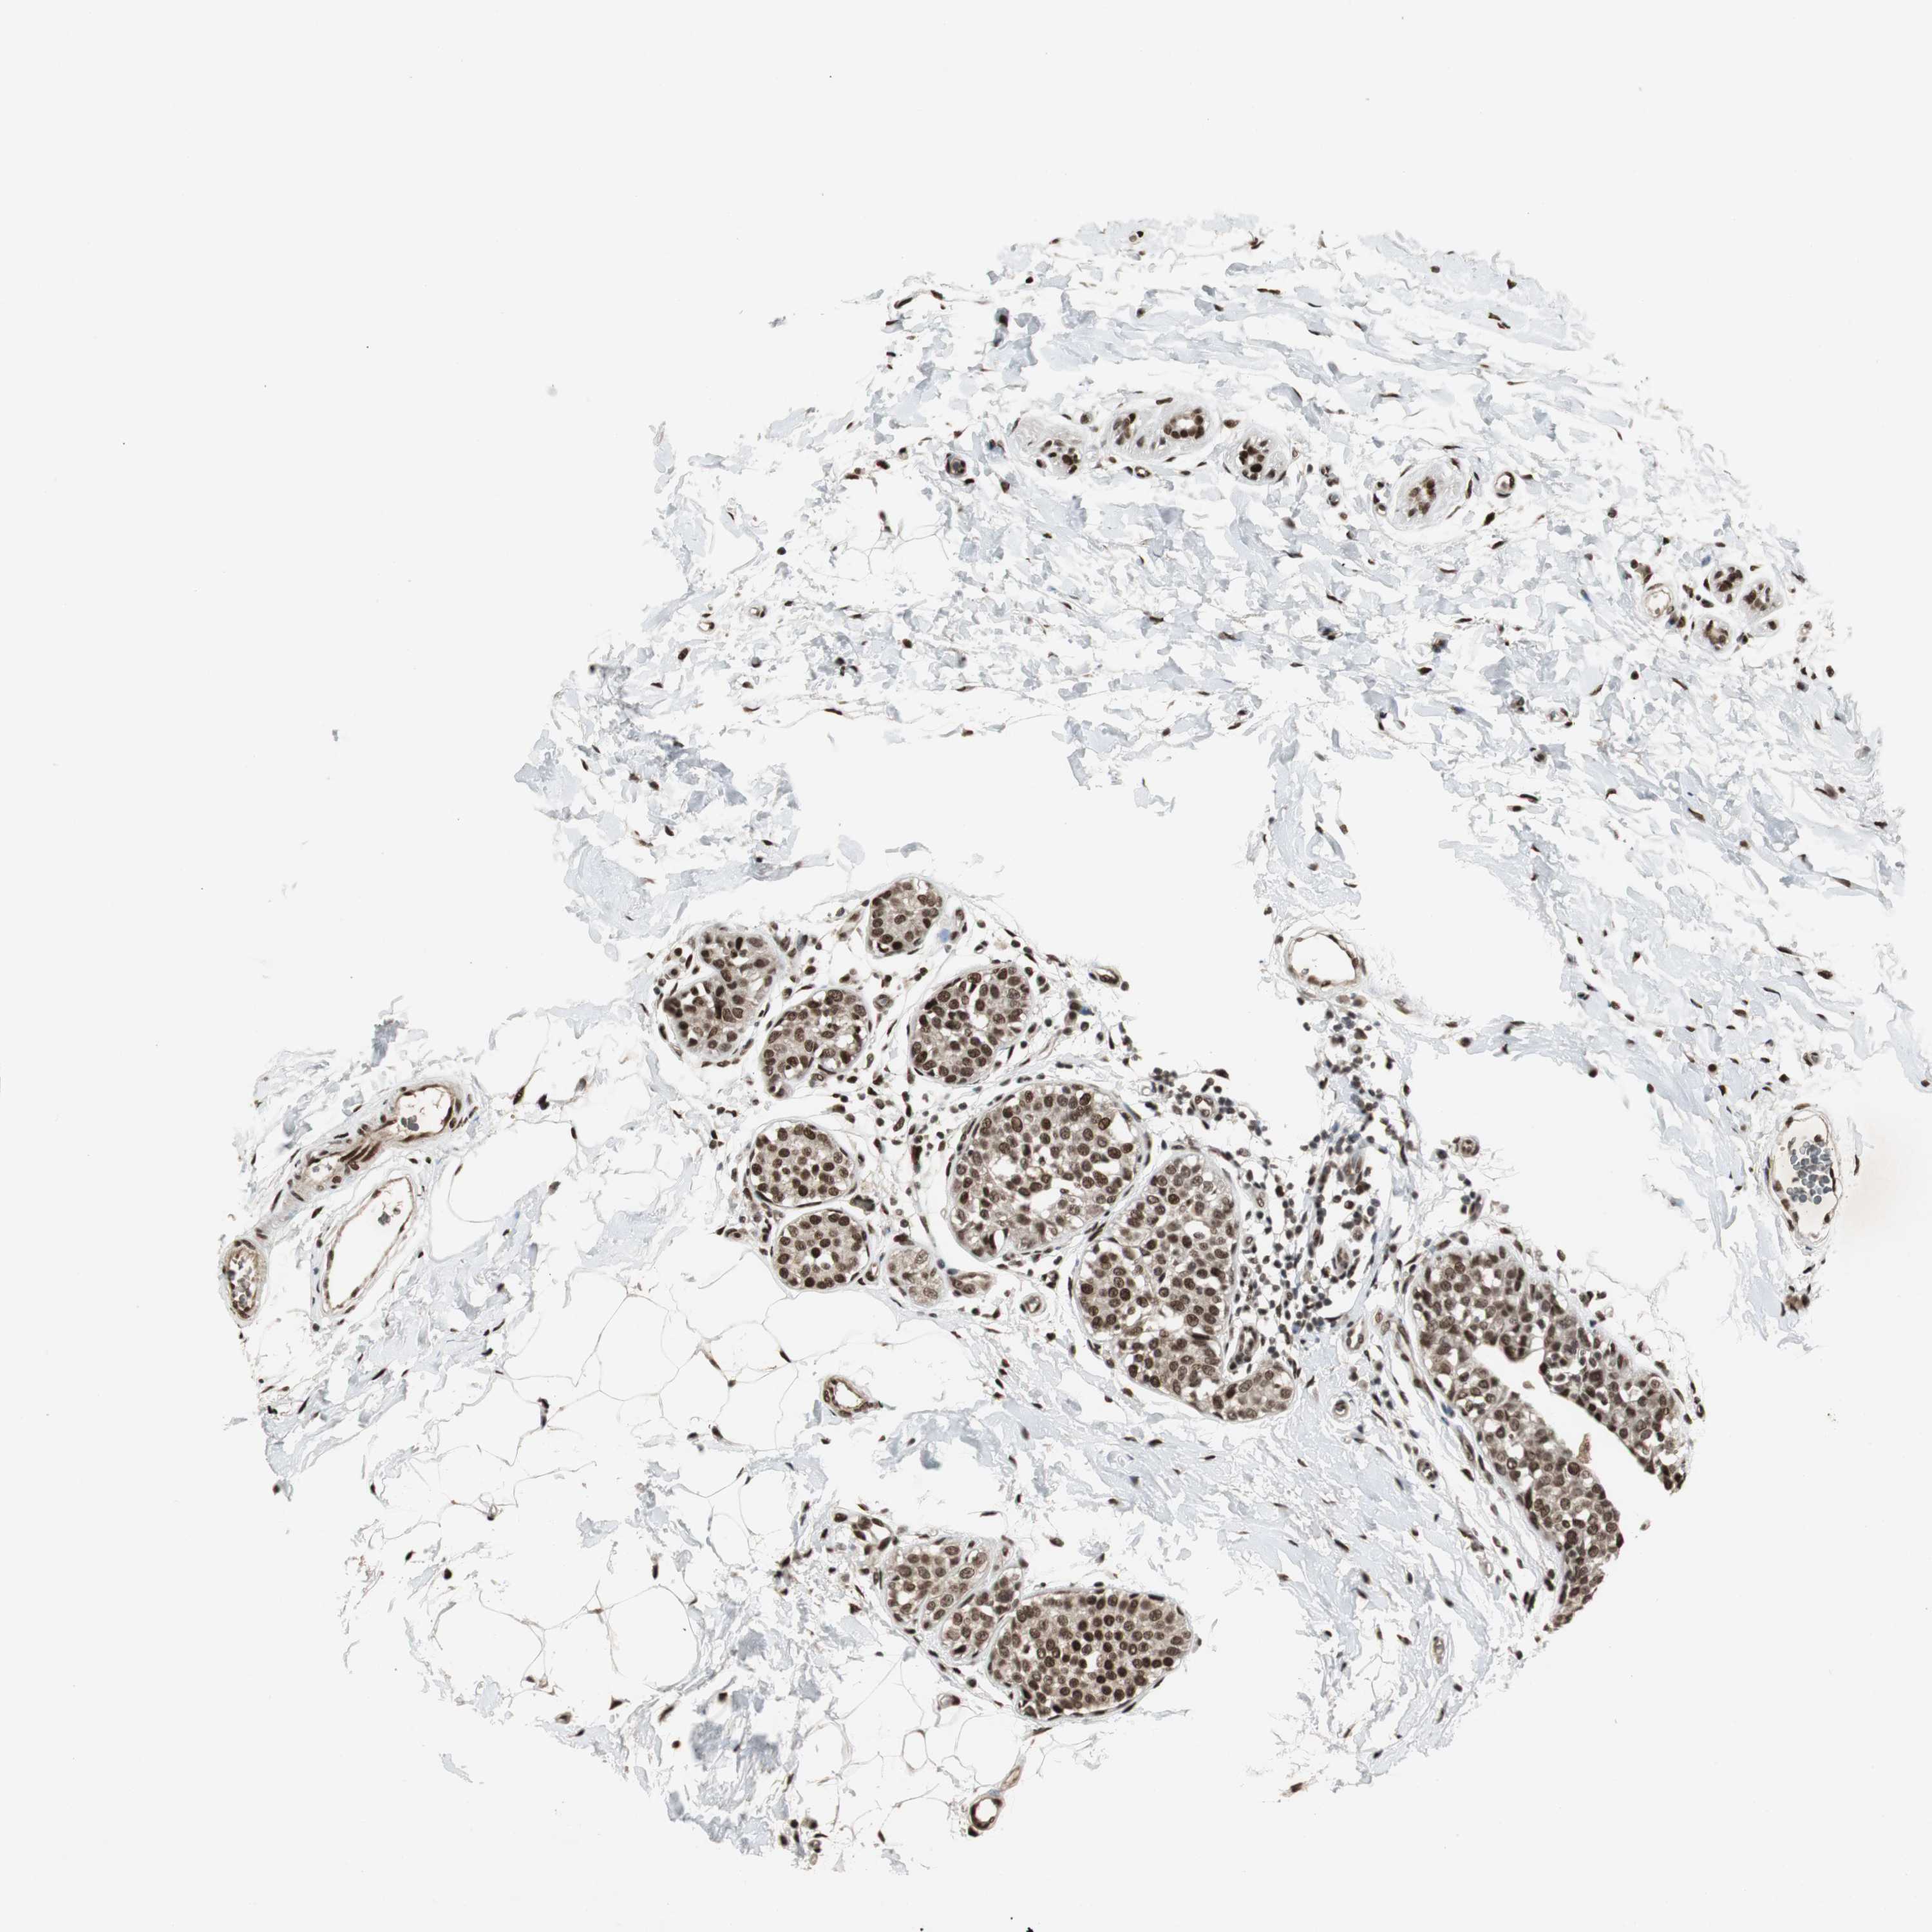

BRCA TCGA BRCA VALIDATION PROTEIN EXPRESSION

ANTIBODIES

AND

VALIDATION